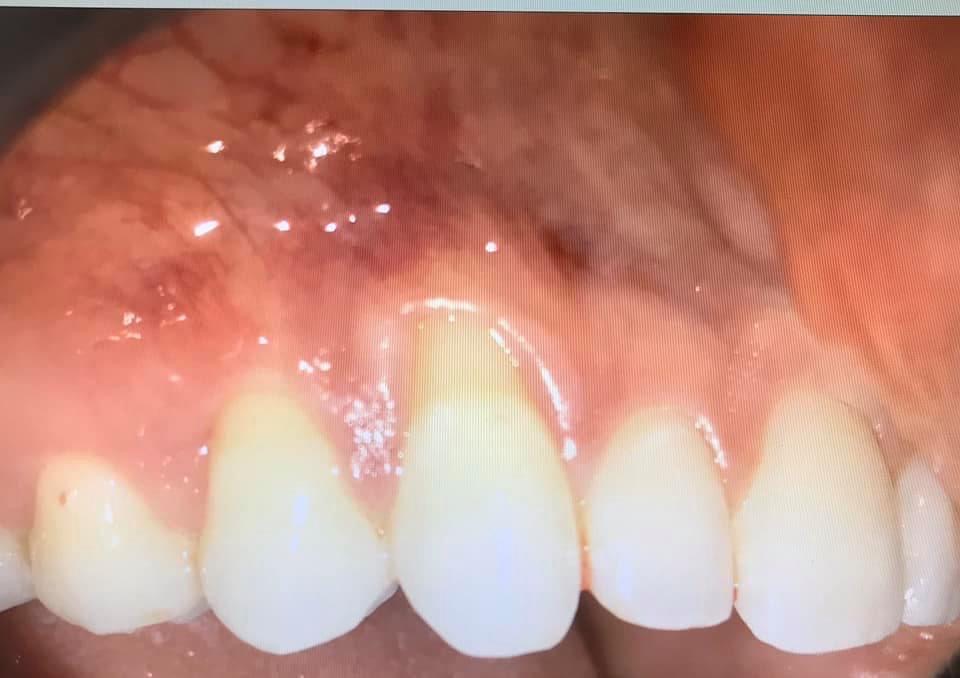

BEFORE AND AFTER PICTURES: